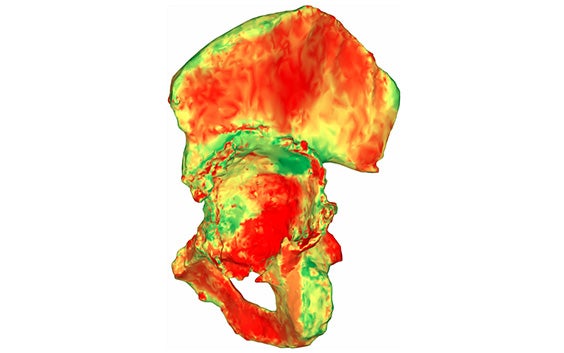

Des analyses pelviennes en 3D uniques

En s'appuyant sur l'examen de tomodensitométrie segmentée, nos ingénieurs cliniciens expérimentés utilisent une technologie basée sur l'IA pour quantifier la perte osseuse acétabulaire et la masse osseuse disponible en mesurant l'épaisseur de l'os et du cortex sur toute la surface.